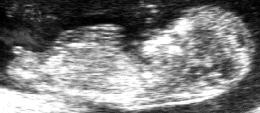

8 числа, целый день ушёл на сдачу анализов и обход врачей, который я оттягивала. Ещё была на УЗИ (на сроке ровно 18 недель), направили, с щитовидной и почками. Без сюрприза не обошлось, есть песок в мочевом, летом его не было... Глянули пол малыша, он сидел на мочевом, датчиком немного поводили и немного увидели, но ничего не понятно было, как и пацан так и девка. писюна не увидела, но большая область в области половых губ, но яички вроде выше у мальчиков. Прошерстела инет, похожего не нашла, точнее похоже на это

но только та пимпа была уже, а может и такая, это фото я отредактировала в фотошопе (зарисовала щель), вот оригинал

на этом фото девочка 100% она уже родилась... но щели я не увидела на нашем УЗИ, всё что врач смог зафиксировать, показал, и это было похоже на фото выше.

А вы как думаете, по первому фото УЗИ, кто у нас может быть?

По вчерашнему видео УЗИ, многие говорят, мальчик и видят писюн, но я и вижу его и не вижу, то есть там где вижу, если всматриваться и ловить каждый миг, то потом это может быть продолжение ноги... в некоторых моментах вижу вод такой наклон, что означает девочка...